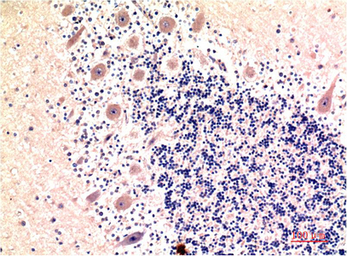

IHC-P analysis of human brain tissue using GTX34068 LC3B antibody [9H5].

Dilution : 1:200